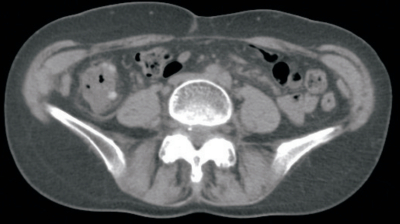

血液所見:赤血球 476万、Hb 15.3 g/dL、Ht 43%、白血球 12,400(好中球 75%、好酸球 1%、好塩基球 1%、単球 4%、リンパ球 19%)、血小板 25万。血液生化学所見:AST 34 U/L、ALT 60 U/L、尿素窒素 12 mg/dL、クレアチニン 0.9 mg/dL。CRP 3.6 mg/dL。腹部単純CTを別に示す。

この画像所見から最も考えられる疾患はどれか。

e. 大腸憩室炎